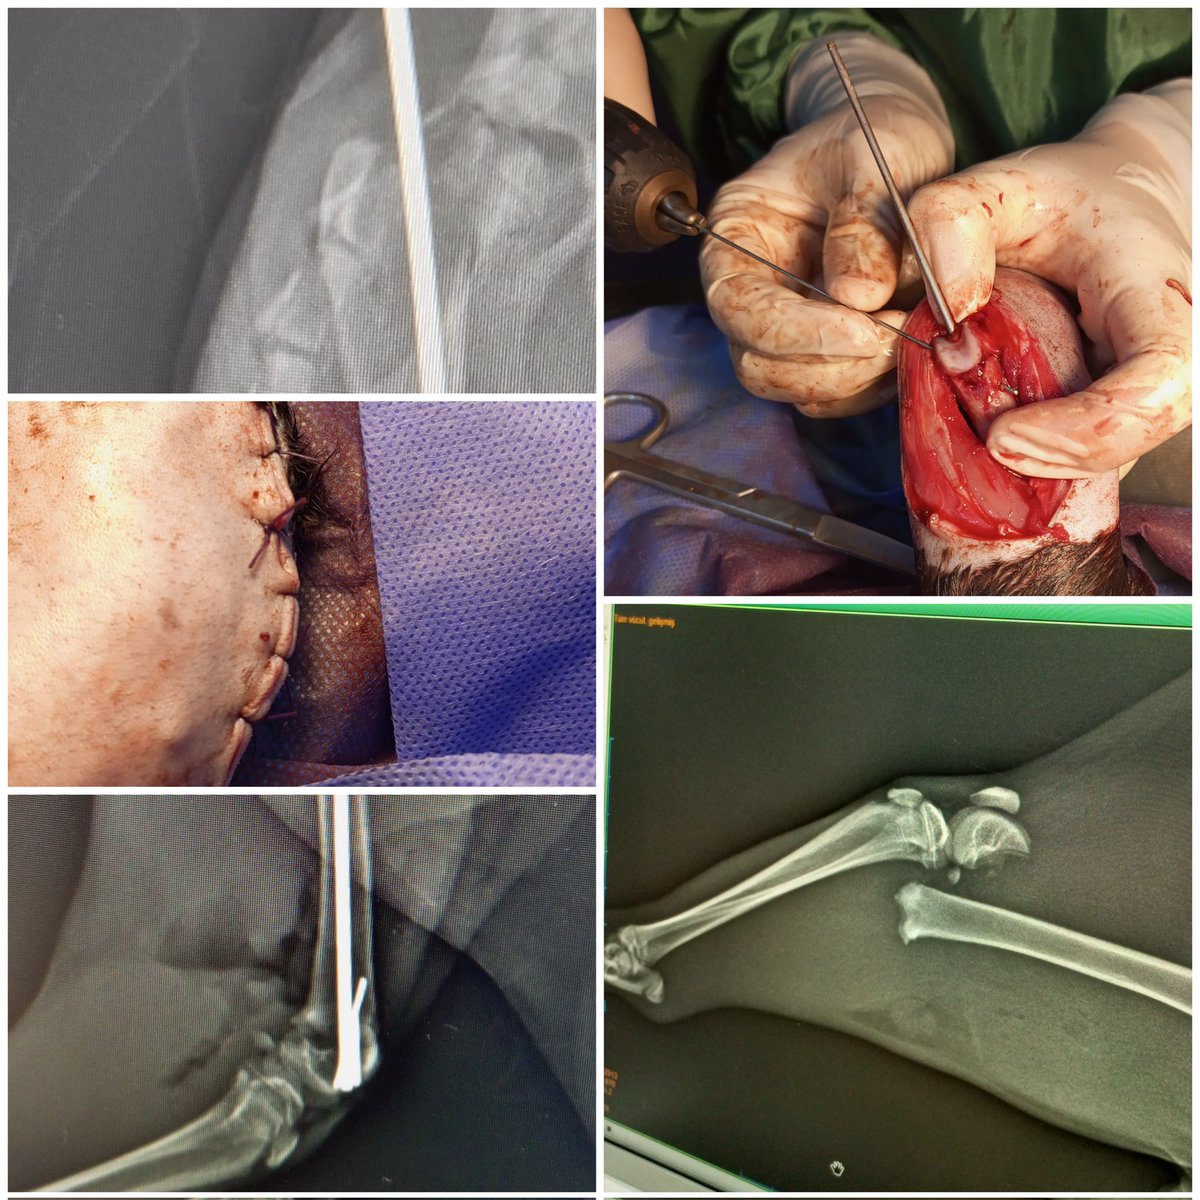

Yüksekten düşme sonucu distal condular ayrılma, intercondular kırık ve damak yarığı olan kedimizin operatif sağaltımı başarı ile tamamlanmıştır. Sağlıklı günlerde tekrar görüşmek dileğiyle 🐾🩷 . . . . #Veteriner #VeterinerHekim #VeterinerKliniği #HayvanSağlığı #EvcilHayvan

Yüksekten düşme sonucu distal condular ayrılma, intercondular kırık ve damak yarığı olan kedimizin operatif sağaltımı başarı ile tamamlanmıştır. Sağlıklı günlerde tekrar görüşmek dileğiyle 🐾🩷